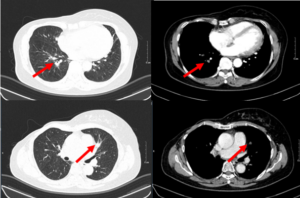

Ca lâm sàng: Hiệu quả điều trị đích bằng Osimertinib ở bệnh nhân ung thư biểu mô tuyến của phổi giai đoạn IV có đột biến gen EGFR L858R (Exon 21) tại Trung tâm Y học hạt nhân và Ung bướu – Bệnh viện Bạch Mai

Ca lâm sàng: Hiệu quả điều trị đích bằng Osimertinib ở bệnh nhân ung thư biểu mô tuyến của phổi giai đoạn IV có đột biến gen EGFR L858R (Exon 21) tại Trung tâm Y học hạt nhân và Ung bướu – Bệnh viện Bạch Mai GS.TS Mai Trọng Khoa,...